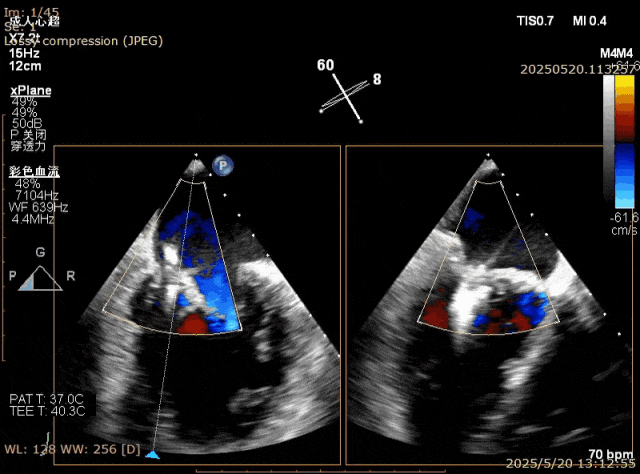

图1. 房间隔穿刺处肥厚,GC难以通过房间隔

图5. Barlow样改变,A3,P2, P3脱垂,后叶甩动厉害